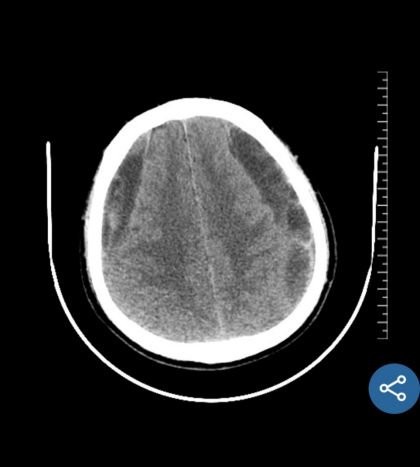

近期,我科完成了一例慢性硬膜下血肿手术。该患者男性,63岁,是因为“摔伤头部半年,记忆力下降,思维迟钝大约20天” 在当地医院就诊,行颅脑CT提示双侧额颞顶部慢性硬膜下血肿,脑疝,CT片可见慢性血肿有很多分隔。当地医院医生建议患者分二次行双侧开颅手术,清除硬膜下血肿,创伤很大,手术后需要住ICU,而且住院时间很长,费用高。患者家属犹豫不决,担心手术风险,于是带着CT片到我科门诊咨询。门诊孟主任阅片后告知家属,我科可以通过神经内镜微创手术治疗慢性硬膜下血肿,可以一次手术,手术创伤小,风险低,费用少,住院时间短,大约10天左右就可以出院,而且手术后不需要住ICU,于是家属当天下午就驱车带患者来我科住院。管床医生涂医生仅用一天时间就完成全部术前检查,第二天就安排了手术。手术中通过神经内镜观察到慢性硬膜下血肿有很多的分隔及纤维组织,与可自行流出的液态慢性血肿相比,该患者需通过吸引器反复仔细吸除血肿分隔及纤维组织,同时反复盐水、双氧水冲洗,避免血肿残留及复发。手术过程很顺利,术后患者清醒,无任何神经功能障碍及并发症,手术后10天患者治愈出院,在后期随访观察中,未见慢性血肿复发。

术前磁共振